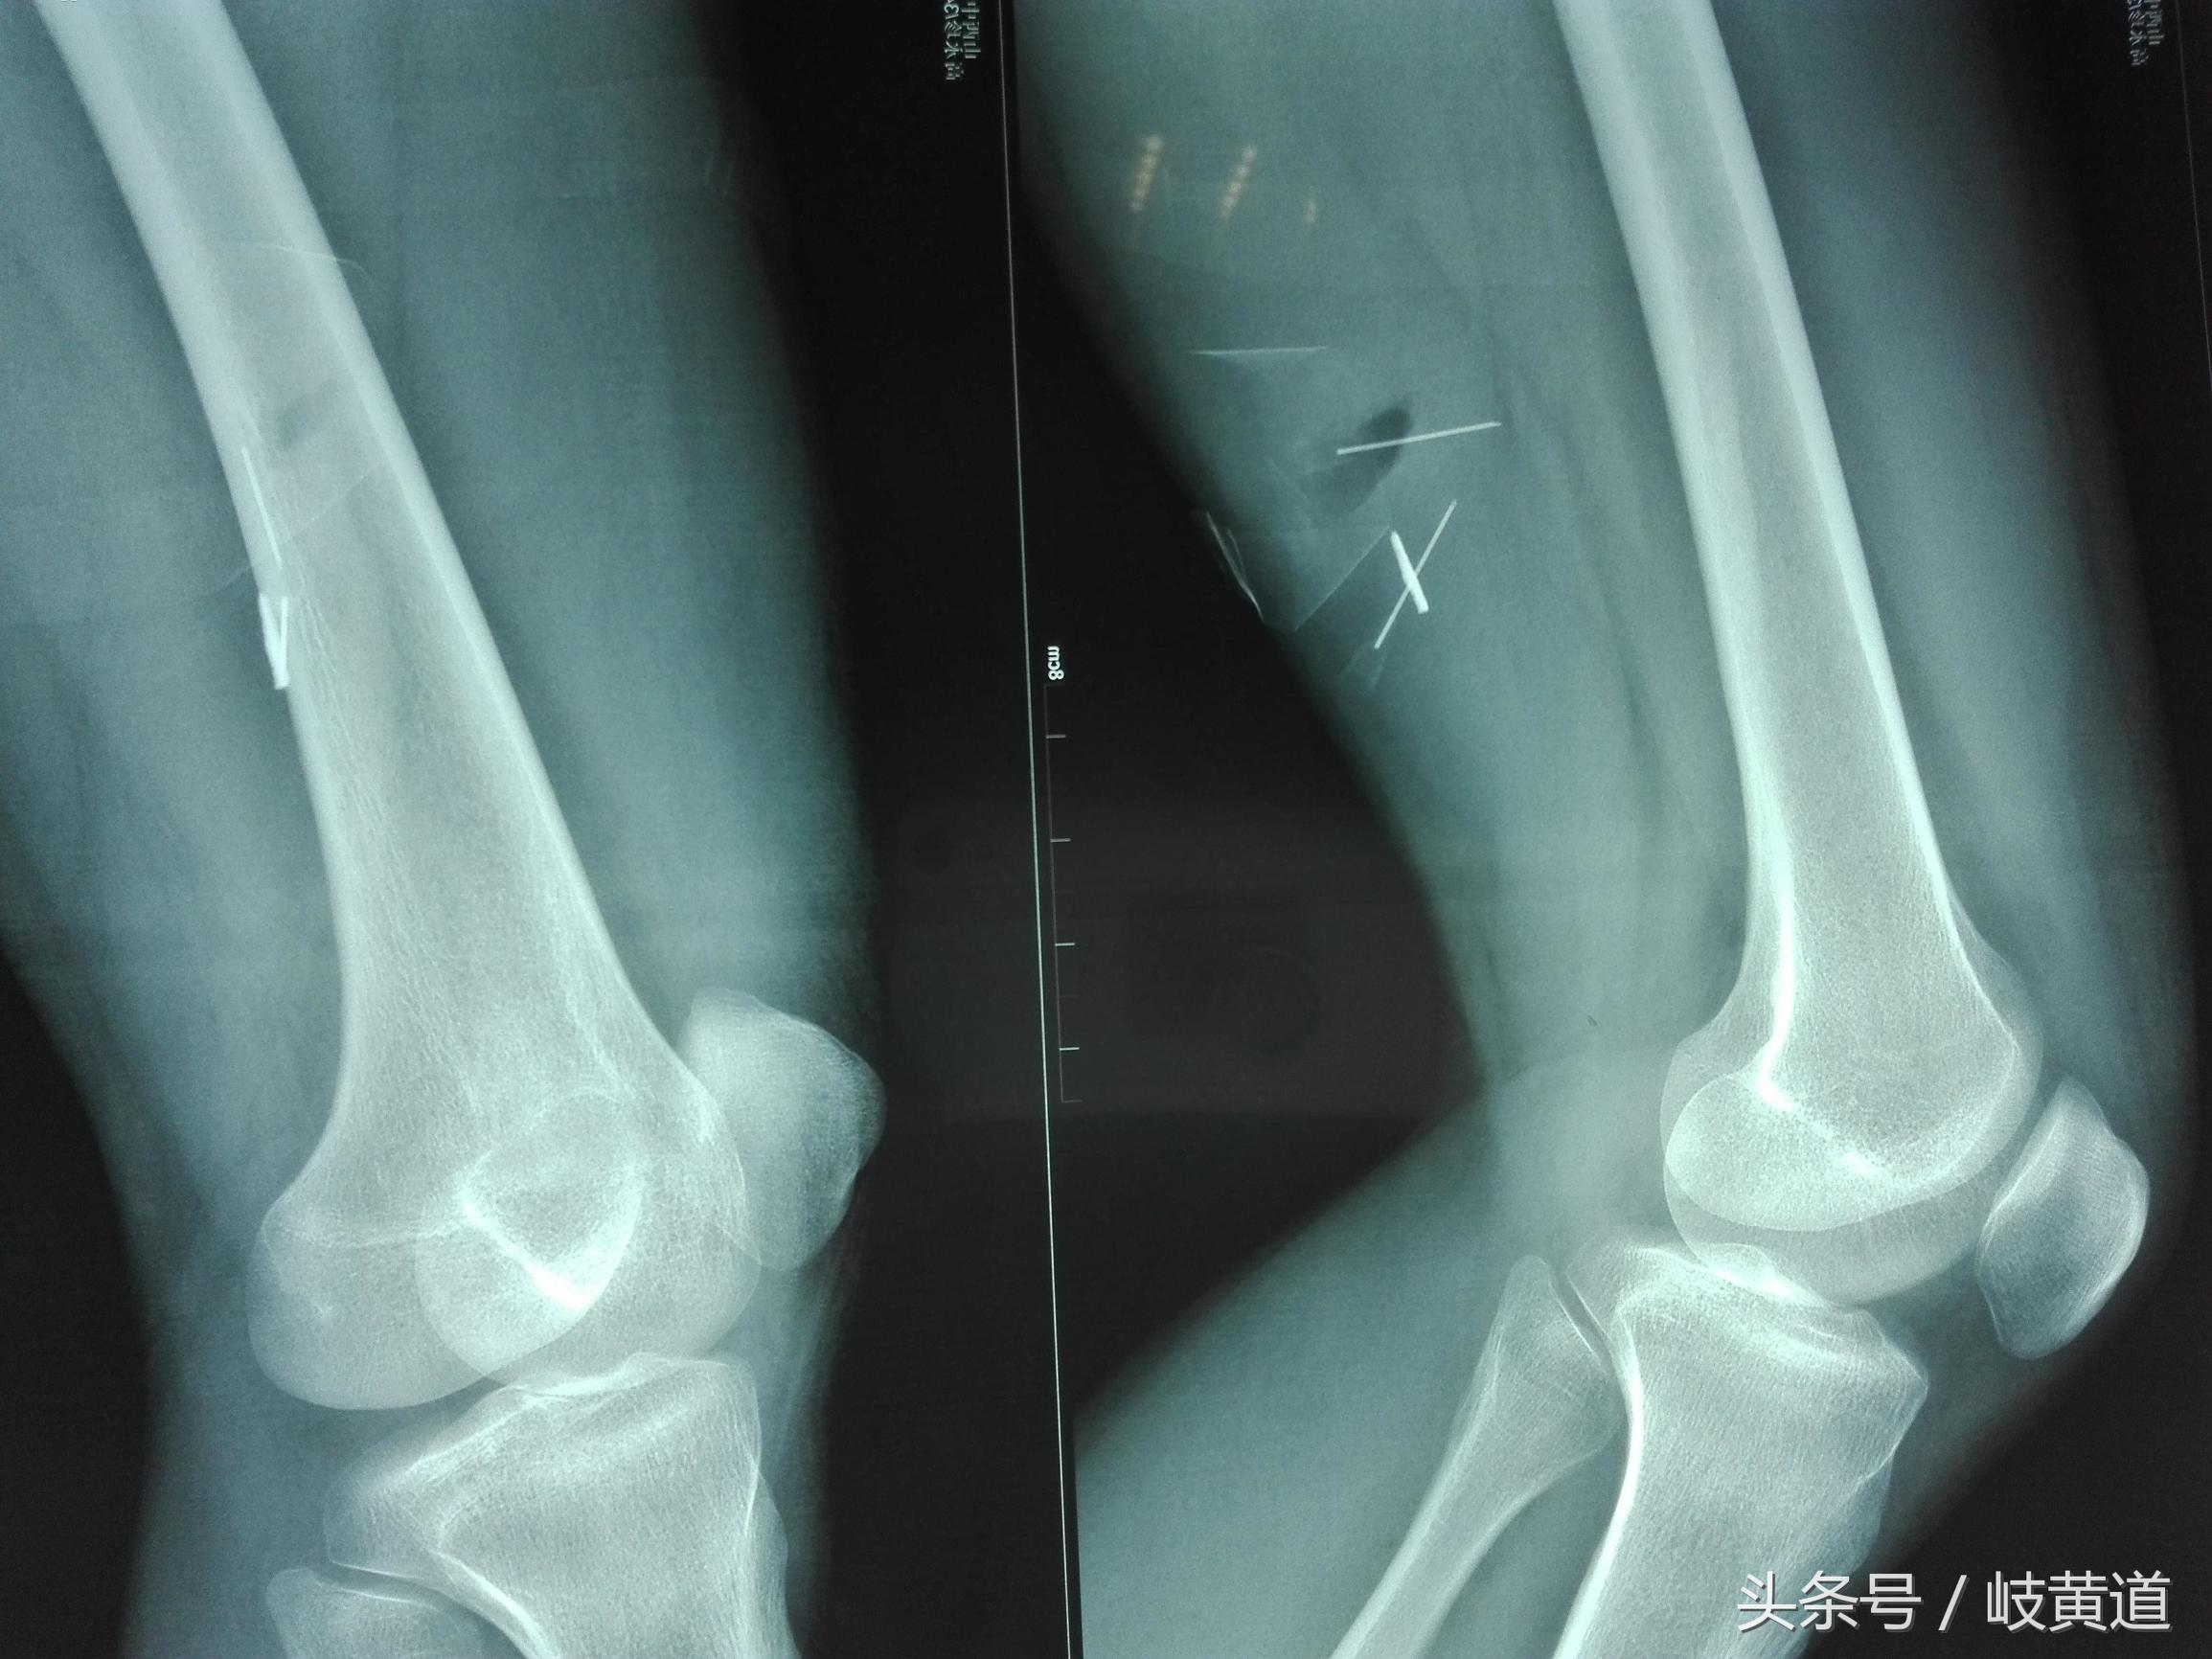

这位患者是下午被工友背进急诊室的,说是大腿扎了个钢渣,当时右大腿内侧靠近膝关节的地方有一个约2mm的小洞,有少量渗血,查体局部摸不到异物,股静脉和大隐静脉没有损伤,于是让他去拍个局部的X线片。

拍了X线片后可以清楚的看到右大腿内侧肌层有一个约2厘米长的棒形异物,于是我们决定:对室内进行常规消毒后直接在透视床上就地展开手术“切开探查取异物”。因为:第一,患者的异物距体表至少有4厘米,比较深且距股动脉很近,稍有不慎异物就有可能划伤股动脉。股动脉一旦破裂其喷射压力相当于高压水枪,后果严重;第二,肌肉已将异物包绕推移,在搬动活动下肢异物的位置还会移动,不好掌控;第三,在透视机上做手术,可以随时拍片定位。经过2次定位和2小时的紧张手术成功取出异物,手术过程虽然有困难,但总算在没有造成严重后果的情况下取出异物。